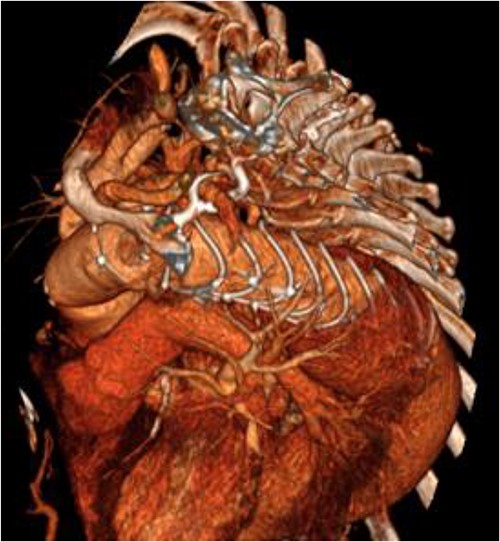

A 67-year-old female with a history from renal impairment and chronic obstructive pulmonary disease (COPD) as an ex-smoker, presented with a known type 2 TAA. A CT aorta showed an aneurysm starting from the left subclavian artery to the aorto-iliac bifurcation. This measured 52 mm in diameter distally near the bifurcation and 50 mm at the descending aorta. Similarly, the distal aortic arch was dilated at 35–40 mm, and the distal ascending aorta was 45 mm and calcified (Fig. 1).

An 8 mm Gelweave graft was anastomosed to the left subclavian artery. Standard cannulation technique was used with the distal aorta and the right atrium. The distal aorta was sized and a 30/32 mm (15 cm length) Thoraflex graft was anastomosed with 4–0 prolene and reinforced with 1.5 cm Teflon. The supra-aortic vessels were reimplanted separately; deep hypothermia (20°C) was utilized for neuroprotection with antegrade cerebral perfusion and near infrared spectroscopy monitoring. Proximal aorta anastomosis followed patient rewarming. Her post-op CT aorta showed adequate perfusion and FET placement. A 3D reconstruction is shown in Figs 2 and 3. She was discharged on Day 10 and successful TEVAR was undertaken 8 months later (Fig. 4). Follow-up 24 months later showed no evidence of endoleak, stent migration or fracture.

3D reconstructed CT aorta image showing successful FET implantation at zone 0.